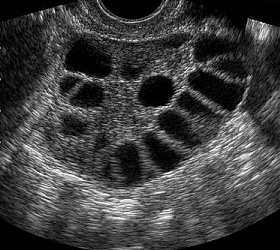

[:vi]Hội chứng buồng chứng đa nang(PCOS) là rối loạn nội tiết thường gặp nhất trong phụ nữ ở lứa tuổi sinh sản.Điều trị PCOS chủ yếu là điều trị triệu chứng và triệu chứng kiến người bệnh đến cơ sở y tế nhiều nhất là trình trạng vô sinh.Mục tiêu bài này là đề cập đến các phác đồ lâm sàng dành cho người bị PCOS có chỉ định thực hiện thụ tinh trong ống nghiệm.[:]

Suy buồng trứng là một rối loạn chức năng nghiêm trọng, gây ảnh hưởng trực tiếp đến khả năng sinh sản và sức khỏe tổng thể của phụ nữ. Không chỉ đơn thuần là sự suy giảm chức năng của buồng trứng, tình trạng này còn đi kèm với nhiều biến chứng nguy hiểm, chẳng hạn như...